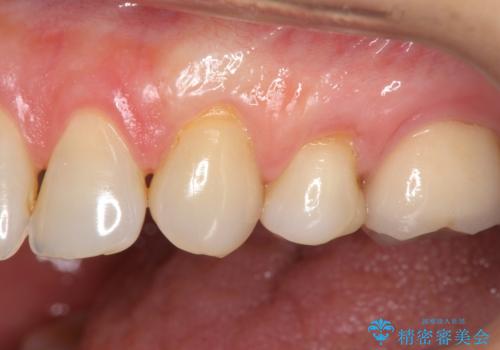

手術を行い歯ぐきの位置が改善することで歯がしみる症状が大幅に改善されたと満足いただくことができました。

手術に合わせて歯ブラシの練習を行うことで再発を未然に防ぐことができます。